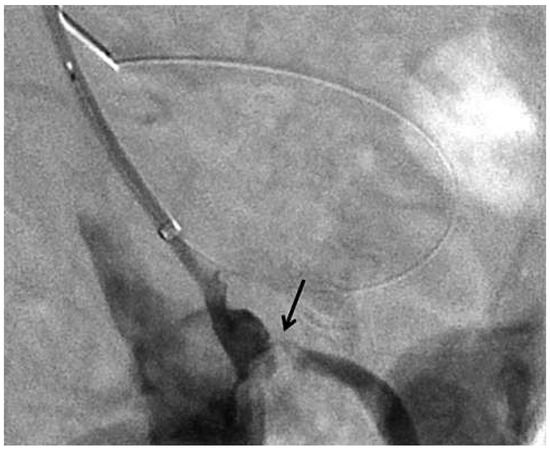

Using a left brachial approach, the coeliac trunk was cannulated with a multipurpose 5F catheter, 125 cm long, inserted over a 6F 90-cm-long sheath. 250 mg aspirin IV and 6000 units unfractionated heparin IV were administered. Angiography revealed a subtotal lesion of the coeliac trunk (Figure 2) and of the superior mesenteric artery (Figure 3). The coeliac lesion was passed with a 0.014” BMW wire (Abbott) and then exchanged over a Minnie Microcatheter (Vascular Solutions) for an Iron Man 0.014” 300-cm-long stiff wire (Abbott). Balloon predilatation was performed with a 4.0 × 20 mm Avion balloon (Invatec) and followed by placement of a 7 × 15 mm Hyppocampus at 14 atmospheres (Medtronic) (final diameter 7.6 mm) with a good final angiographic result (Figure 4). Since reperfusion of one vessel is usually sufficient to reverse mesenteric ischaemia we refrained from approaching the superior mesenteric artery. 600 mg clopidogrel PO were administered at the end of the procedure.

Figure 4.

Digital subtraction angiography of the abdominal aorta showing the final results after stent placement in the coeliac trunk (arrows).